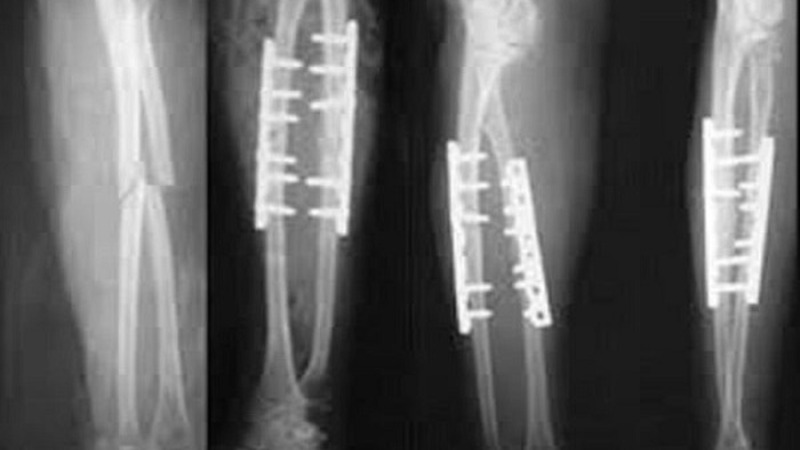

Trong quá trình điều trị gãy xương, việc đặt đinh cố định là một phương pháp phổ biến để đảm bảo xương được giữ vững và hồi phục đúng cách. Tuy nhiên, sau khi xương đã lành, việc mổ rút đinh trở thành bước quan trọng tiếp theo. Một câu hỏi thường được đặt ra là mổ rút đinh bao lâu thì đi được?

Quá trình mổ rút đinh cố định là một phương pháp phẫu thuật nhằm gỡ bỏ các đinh hoặc nẹp được sử dụng để ổn định xương sau chấn thương hoặc phẫu thuật gốc. Quá trình này bao gồm: